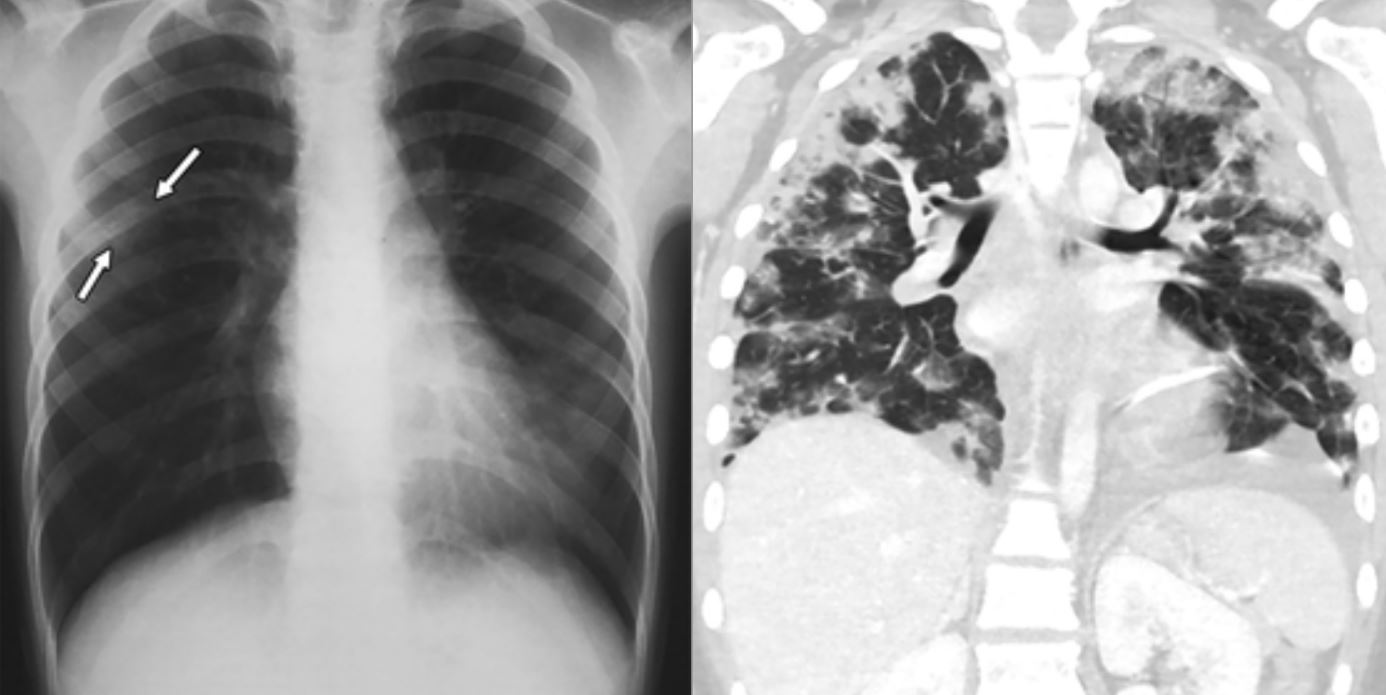

Las imágenes muestran una inflamación generalizada en estos órganos

En los resultados se puede observar que casi dos tercios de los 20 niños menores de 14 años con Covid-19 detectados en Wuhan, China, presentaban opacidad en vidrio esmerilado, un indicativo de que existe una inflamación generalizada, destacó RT.

Además, la mitad de los pacientes mostraban una condición conocida como “el signo del halo”, que hace que la inflamación rodee una masa conocida como consolidación, la cual dificulta la respiración debido a la presencia en los alvéolos pulmonares de sustancias como líquido o infección. La consolidación es un síntoma de neumonía y puede causar problemas respiratorios porque el aire inhalado no puede atravesar la masa obstructora.